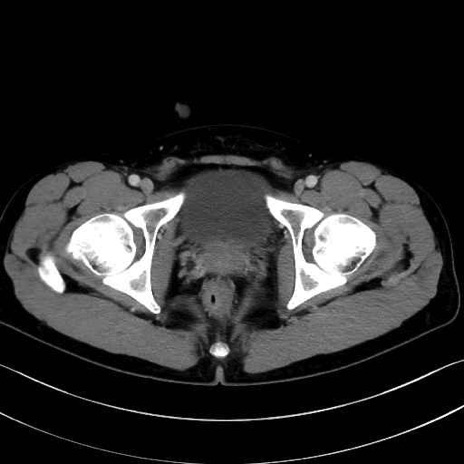

精嚢(seminal vesicle)のCT画像における解剖

症例

【症例】20歳代 男性 スクリーニング